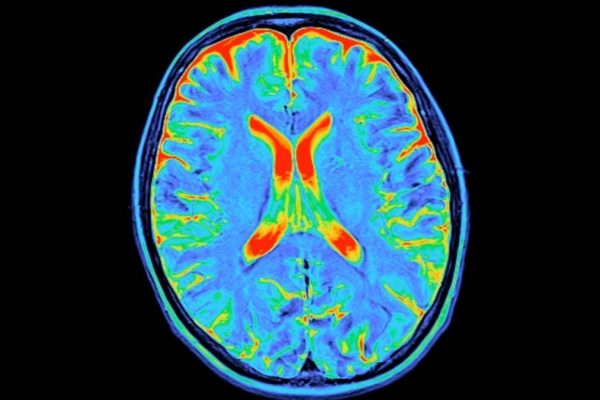

Neuroștiințașii de la Universitatea Cambridge din Marea Britanie și de la Universitatea Pittsburgh din SUA au identificat acum patru momente majore de schimbare în conectivitatea creierului între naștere și moarte. Asemenea capitolelor vieții noastre, fiecare dintre aceste ‘epoci’ neurologice marchează o nouă eră de dezvoltare sau declin. „Privind înapoi, mulți dintre noi simțim că viețile…